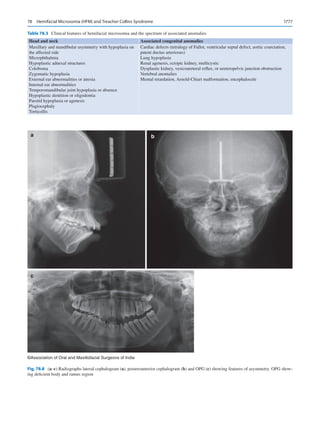

While most standard texts would lead one to believe that

extensive investigations in patients who are supposedly normal

on history and clinical appraisal are not instrumental in improv-

ing outcomes or economically justified, it must be remembered

that these perceptions are built upon data accumulated from the

West, where regular health checkups and assessments are the

norms. In contrast, in countries like India, a patient’s first visit

to a hospital may be for the surgery he is being posted for.

Patients may also not be aware of existing comorbidities or